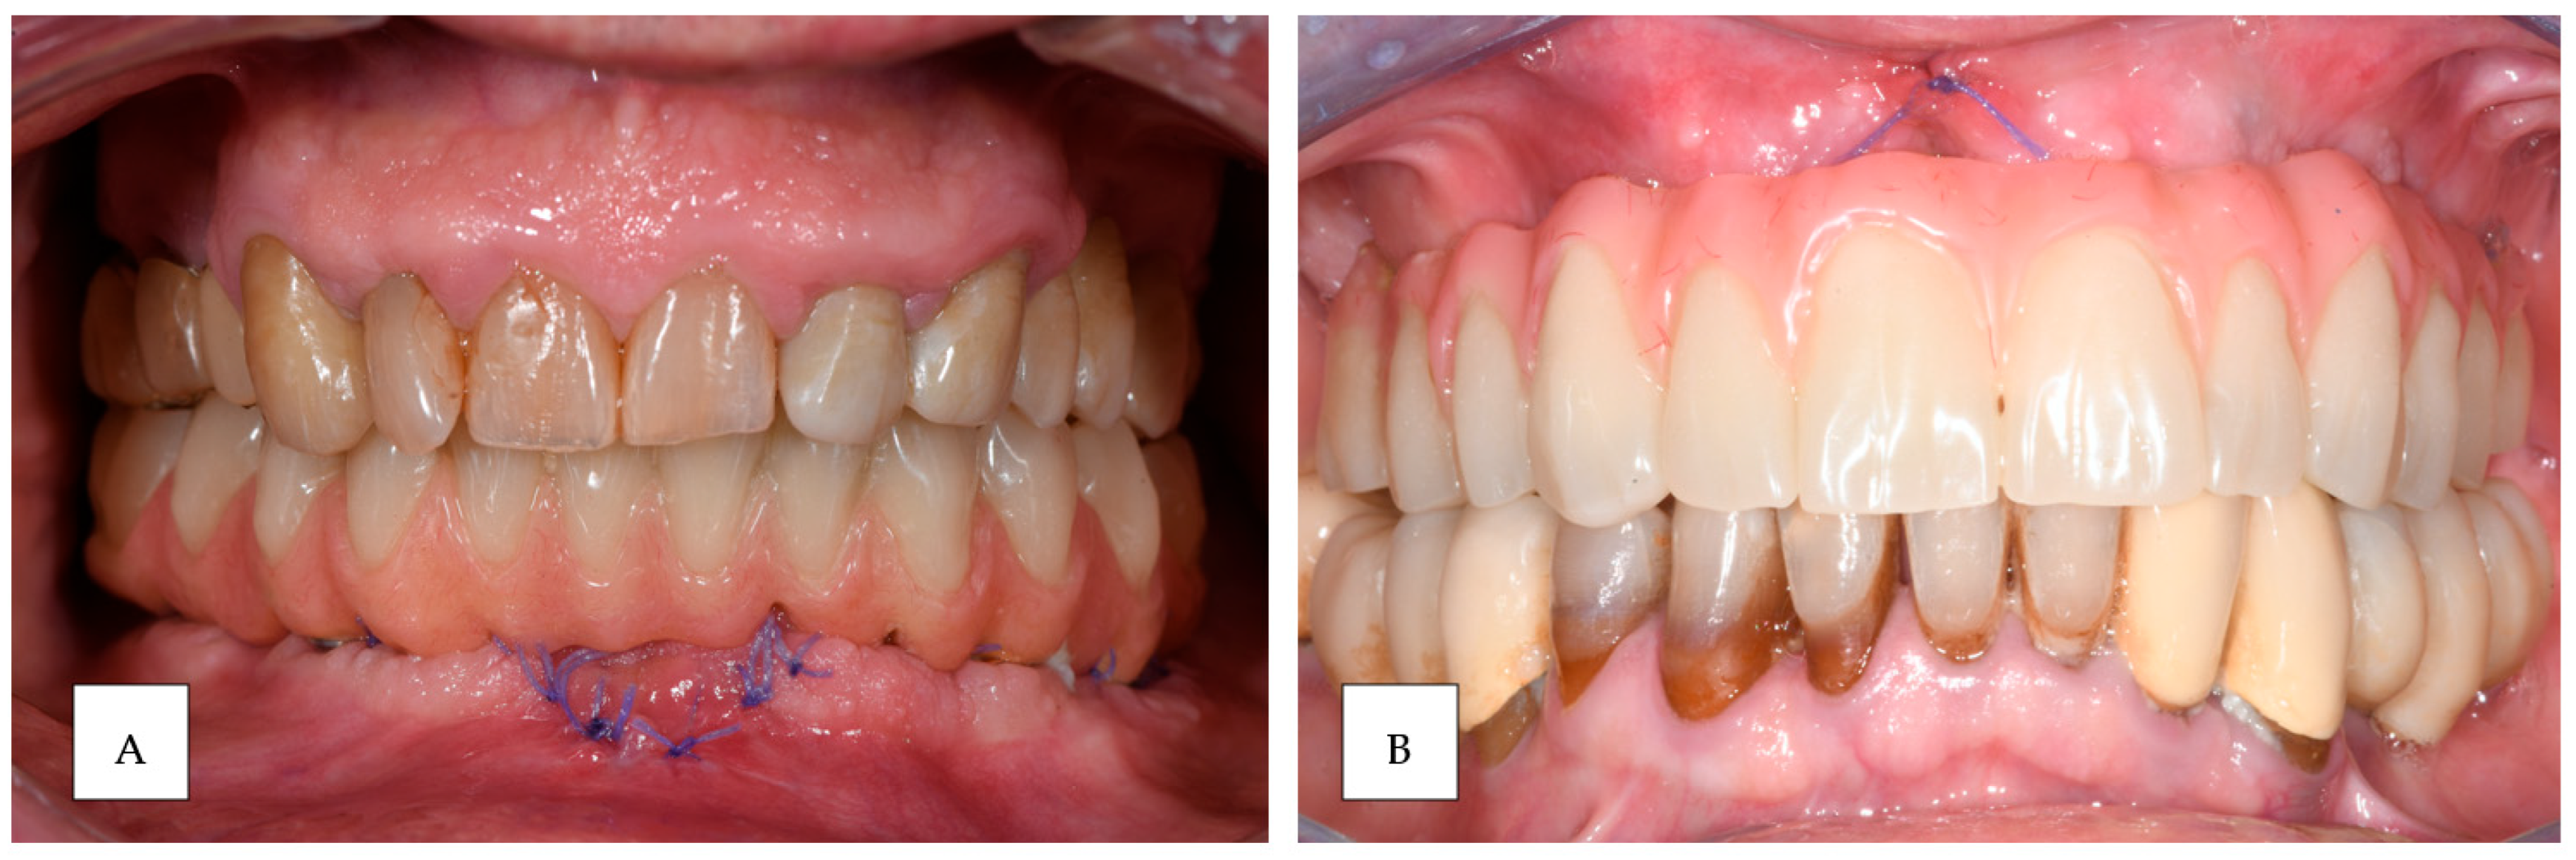

3. Results

2.5. Prosthesis Generation